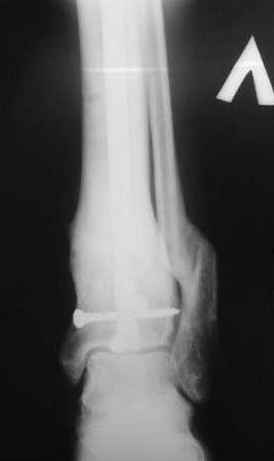

5, 6 - через 2,5 мес после травмы выполнен закрытый остеосинтез блокируемым штифтом.

7, 8, 9, 10, 11 - через 8 мес после травмы перелом сросся.

Пациент ходит без дополнительной опоры, не хромает (видеоролик выложил сюда

http://rapidshare.com/files/14134274/Patient_B.AVI.html, вес 892 кб).